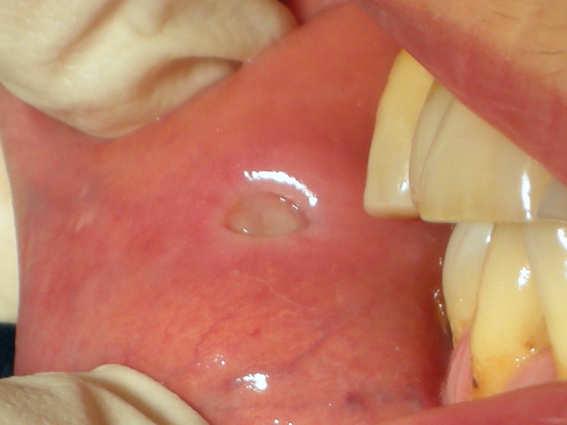

Morsicatio buccarum

Morsicatio buccarum (also known as "Chronic cheek biting," and "Chronic cheek chewing") is a cutaneous condition characterized by chronic irritation or injury to the buccal mucosa from repetitive chewing, biting or nibbling produces characteristic changes in the tissue.